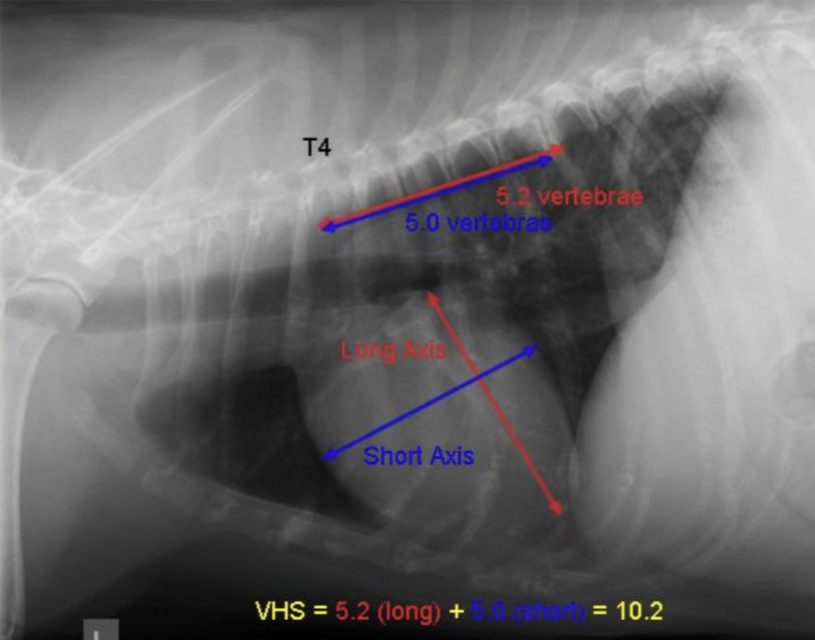

| VHS | Vertebral heart score.![]() | ์ฌ์ฅ ํฌ๊ธฐ์ ์ฒ์ถ๋ผ์ ๋น๊ต. - ์ฅ์ถ : carina์ ventral border์์ ์ฌ์ฅ์ apex๊น์ง (fat ํฌํจํ๋ฉด ์ ๋จ) - ๋จ์ถ : ์ฅ์ถ๊ณผ ์์งํ๊ฒ, CVC ๊ทผ์ฒ์์ ๊ฐ์ฅ ๋์ ๋ฒ์ โ T4 ๋งจ ์์ชฝ๋ถํฐ ์ฅ์ถ/๋จ์ถ ๊ธธ์ด๋งํผ ๊ฐ์ ๋ ์ฒ์ถ๋ผ์ ๊ฐ์๋ฅผ ๋ํจ. Dog : 8.5 Cat : 6.7 |